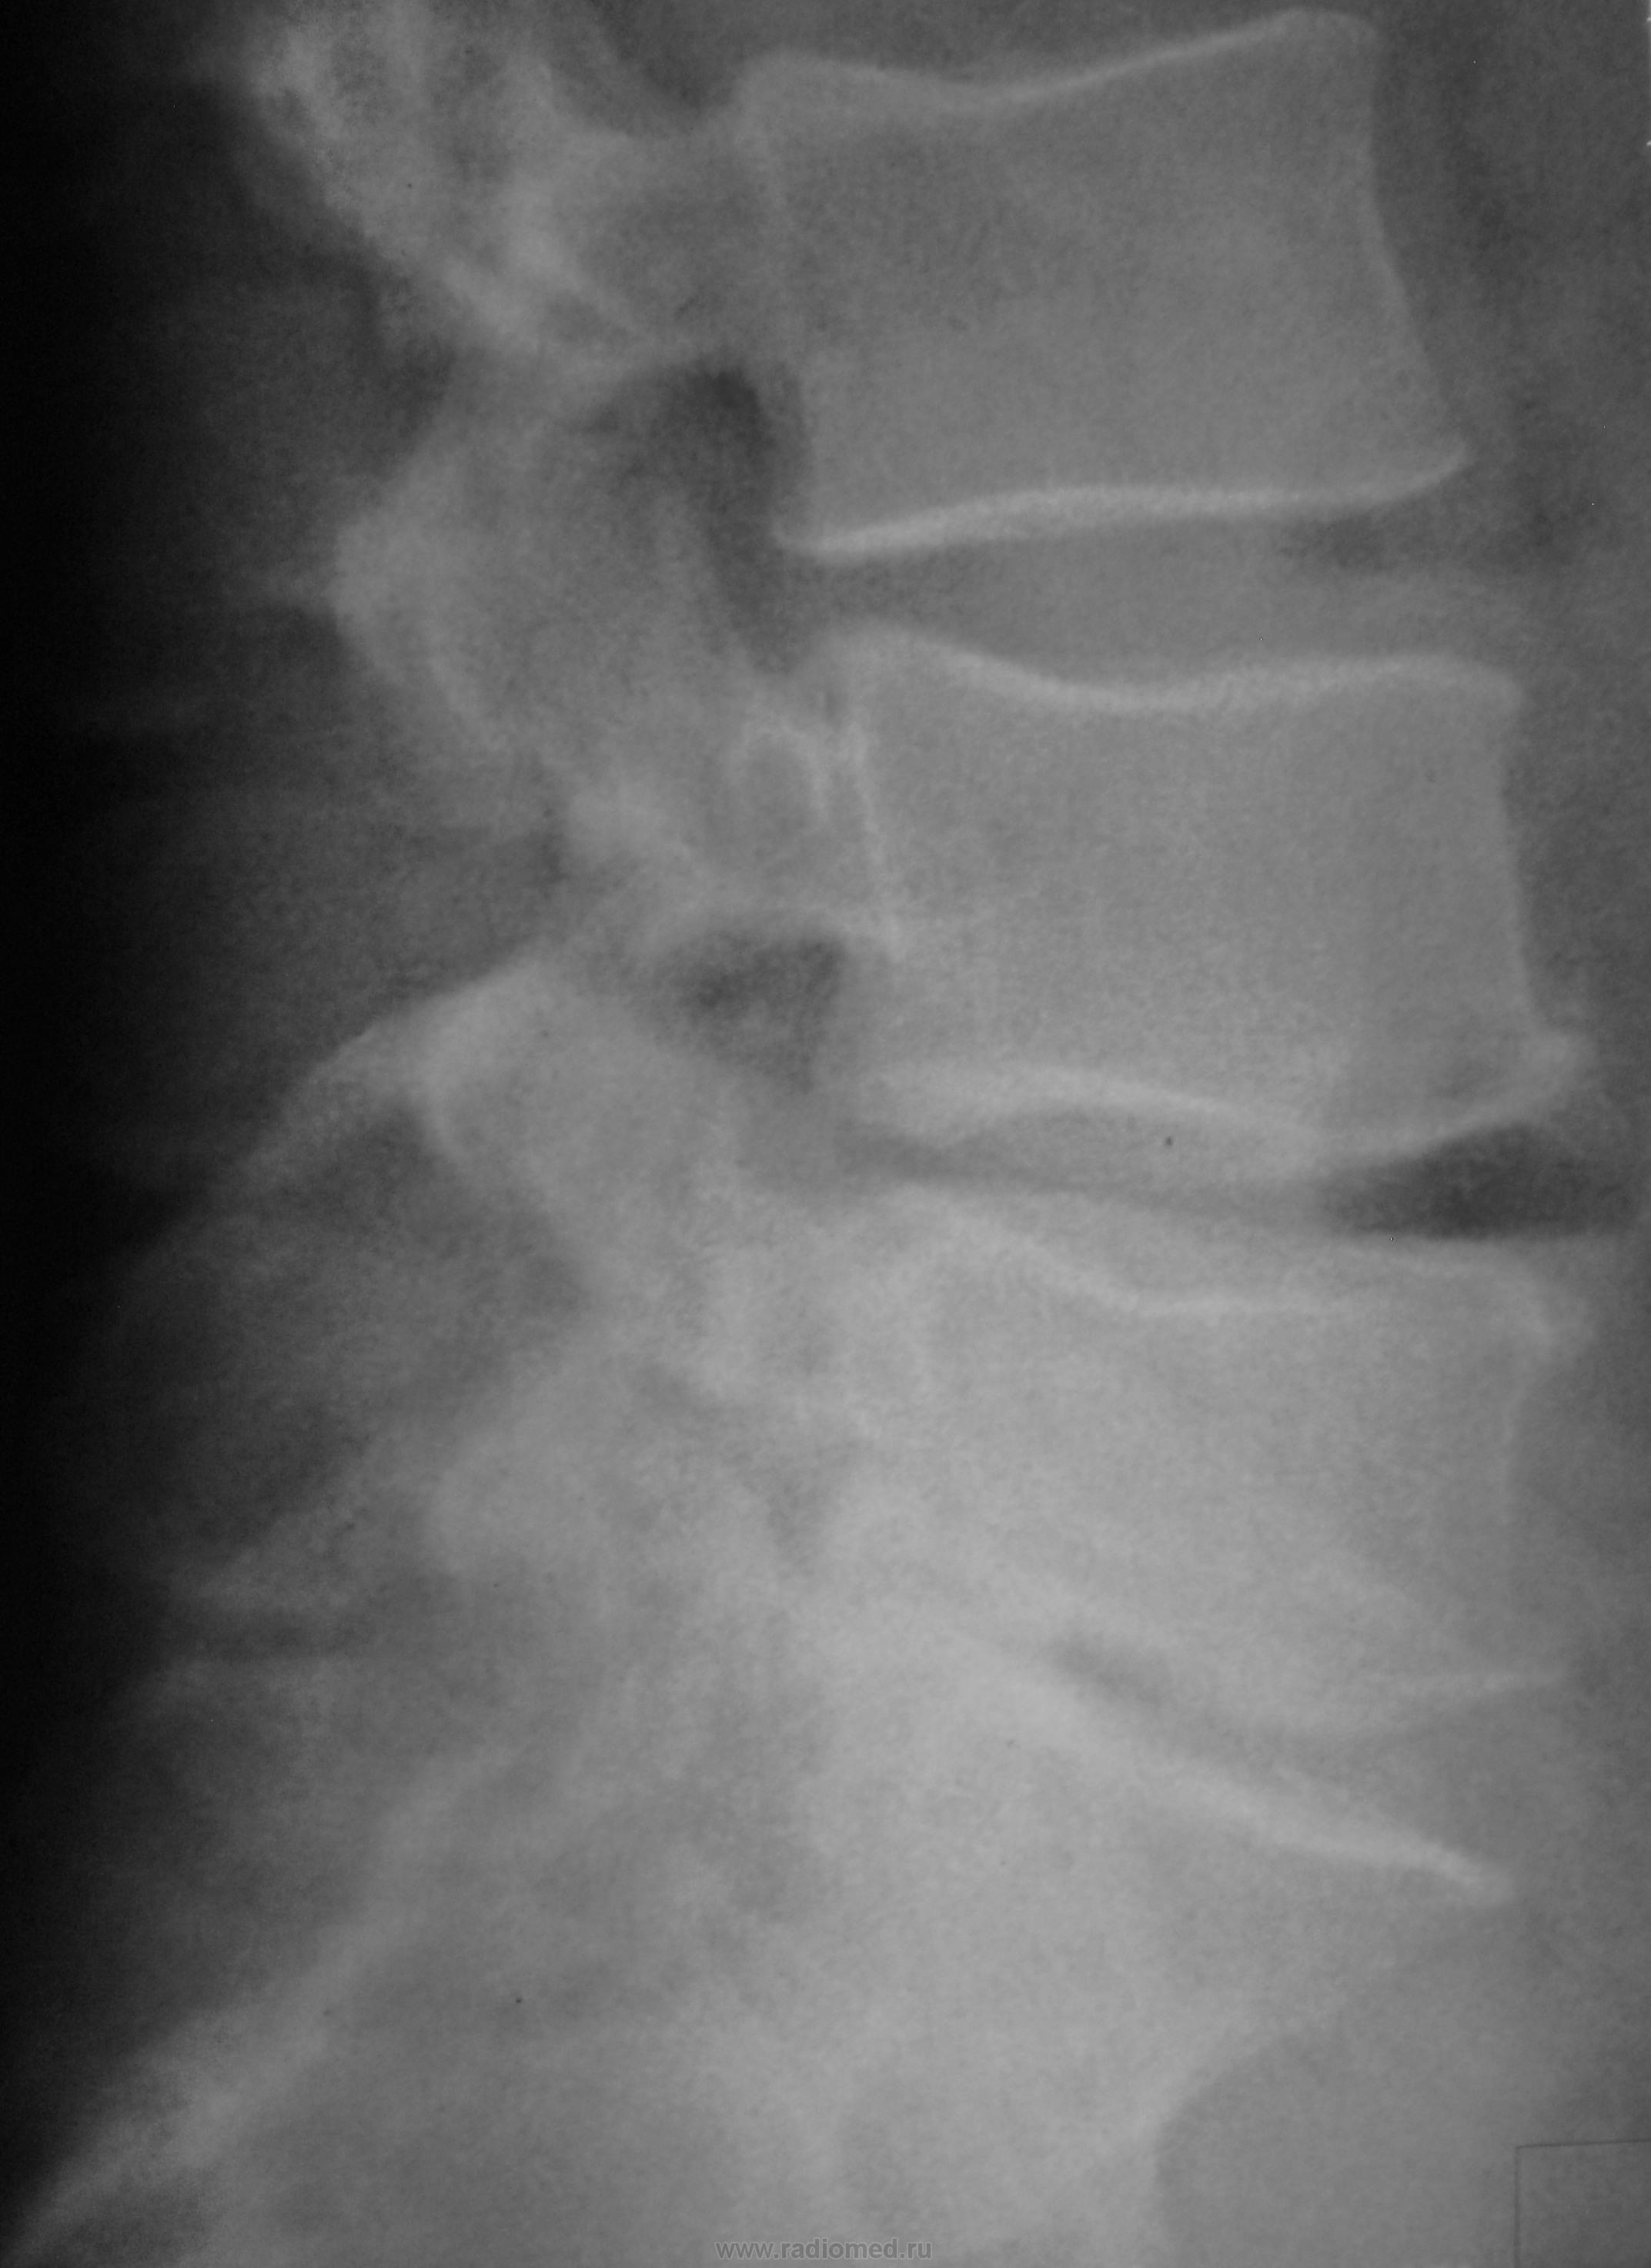

остеохондроз, спондилёз и сколиоз, я думаю, дело уже привычное. Удивило то, что я смог рассмотреть: полная двусторонняя люмбализация S1, спондилолиз S1 и spina bifida posterior S1. такую комбинацию вижу первый раз! может, я не прав!?

spina bifida posterior в L4, или я не прав?

Не согласна. С такой неподготовкой можно много пририсовать. Я бы пересняла, и боковой тоже.

Не всегда, даже тщательная подготовка пациента достигает своей цели. Порой, "голодные газы" могут сыграть злую шутку.